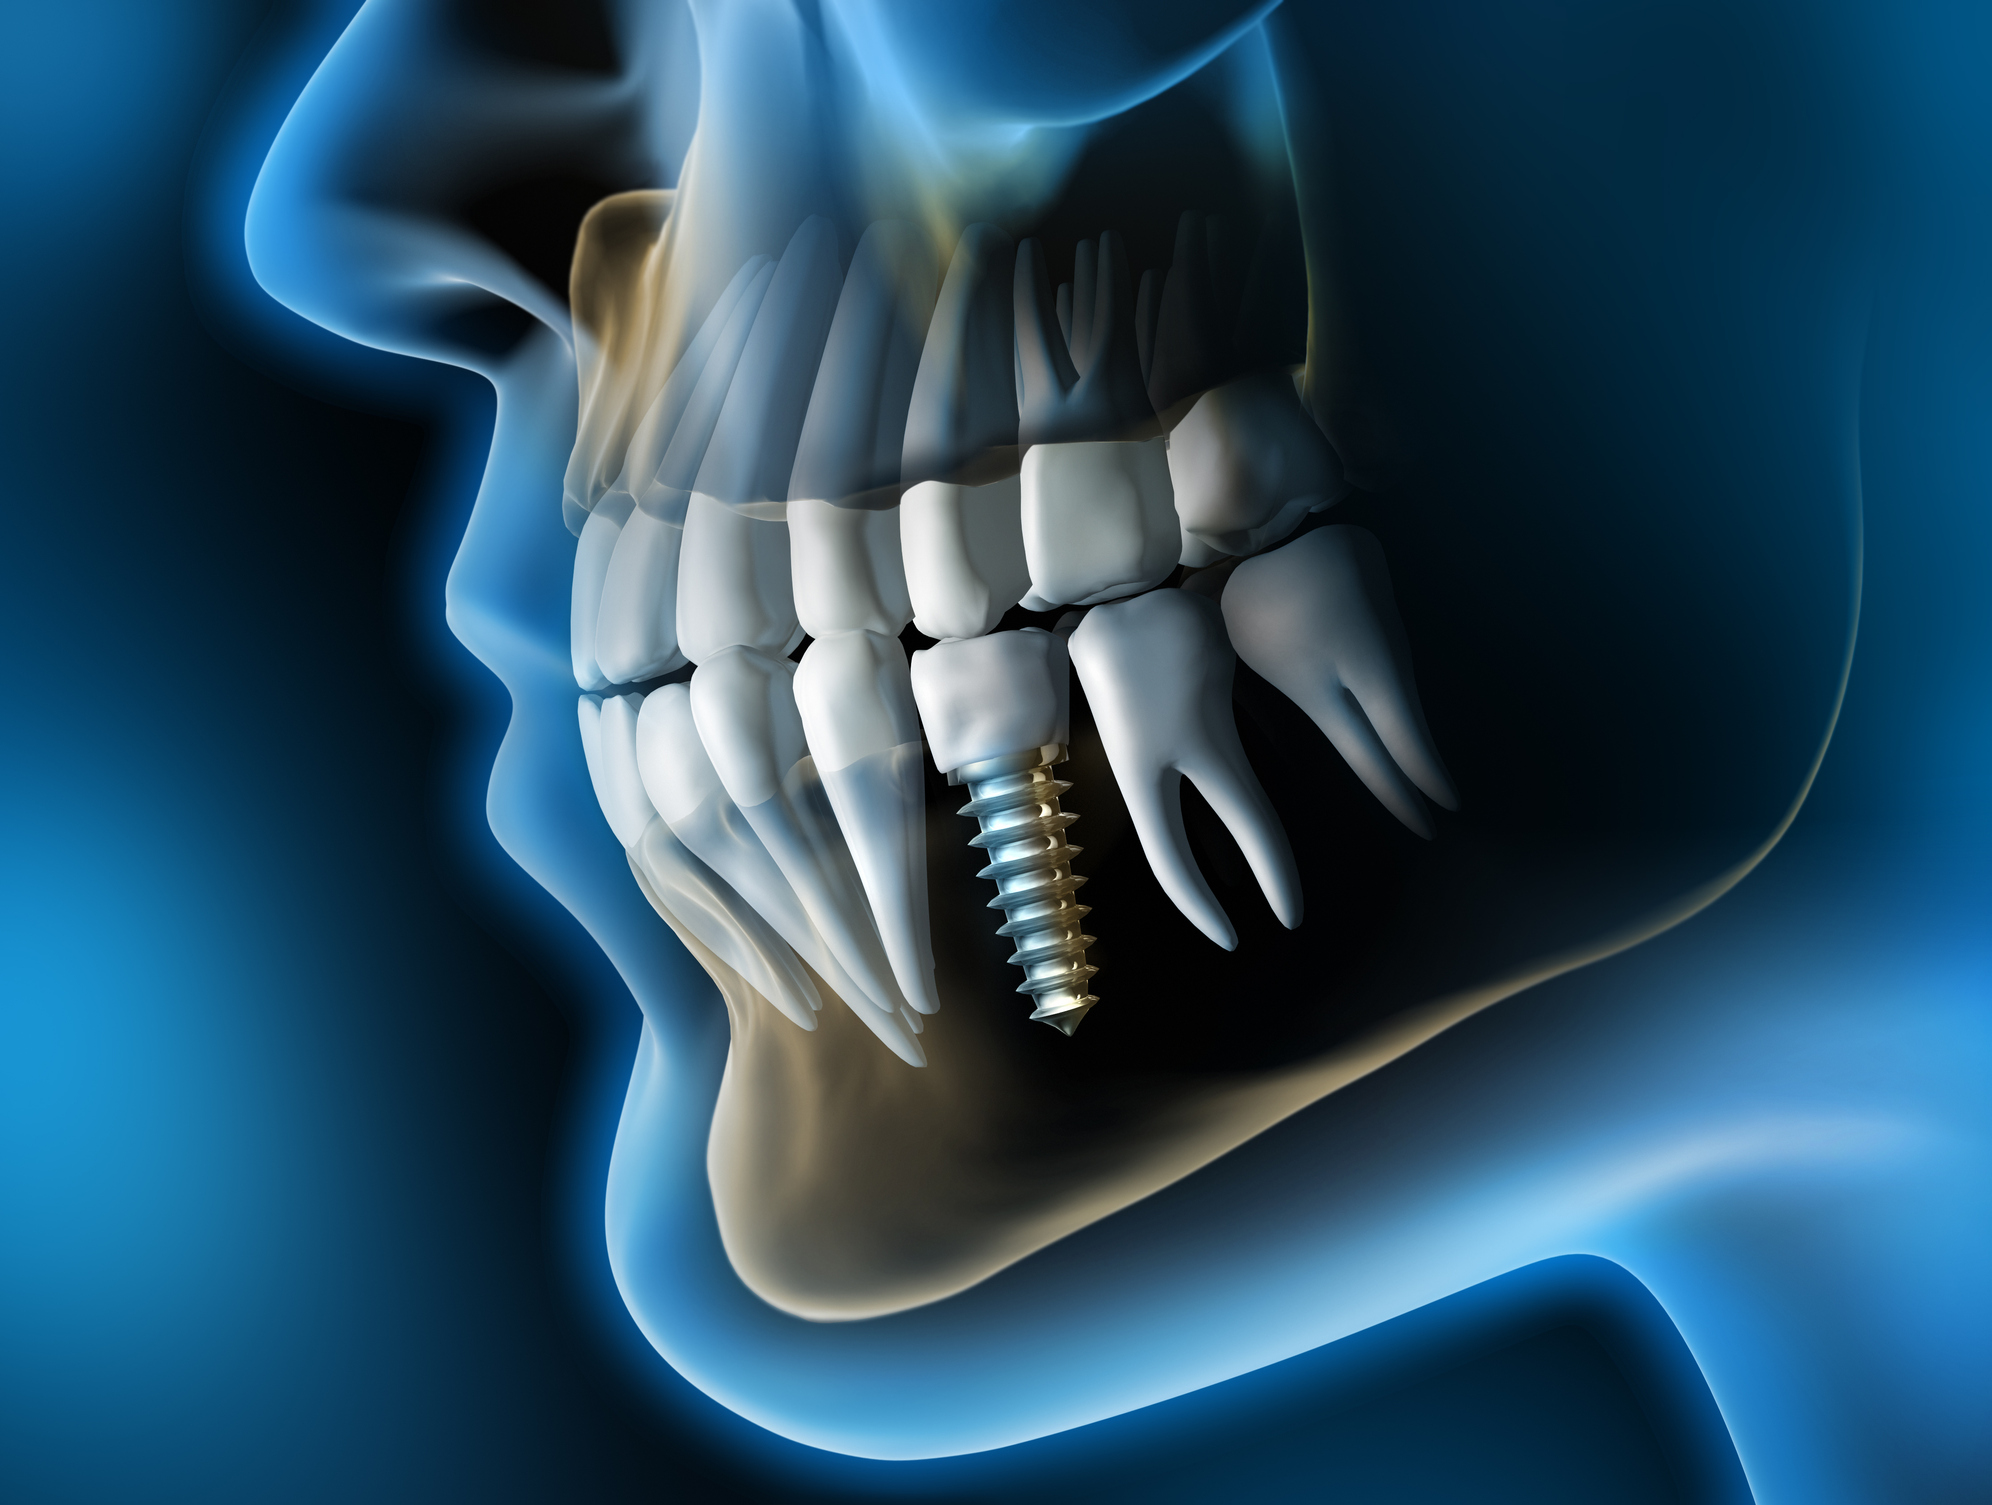

Los implantes dentales son raíces artificiales de titanio o zirconio que se colocan en el hueso maxilar o mandibular para reemplazar dientes perdidos.

Sobre ellos se coloca una corona, puente o prótesis, logrando una función y apariencia prácticamente idénticas a un diente natural.

El implante actúa como la raíz del diente, integrándose al hueso mediante un proceso biológico llamado osteointegración.

Durante este proceso, el hueso crece alrededor del implante, fusionándose firmemente con él, lo que permite soportar fuerzas masticatorias de manera estable y segura.

Bajo anestesia local, se inserta el implante en el hueso mediante una microcirugía mínimamente invasiva.

Una vez que el implante está integrado, se coloca un pilar o conector y sobre éste una corona personalizada, diseñada para imitar la forma, color y brillo del diente natural.